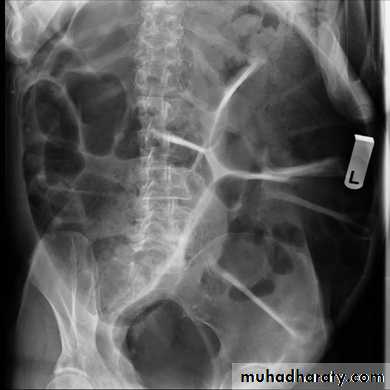

Pneumoperitoneum

Defined as free gas in the peritoneal cavityThe commonest cause is perforated peptic ulcer and two-thirds of such cases are recognizable radiologically

Free intraperitoneal air is a normal finding after a laparotomy or laparoscopy.

In adults, the air is usually absorbed within 7 days .

In children, the air absorbs much faster ,usually within 24 hours.

An increase in the amount of air on successive films indicates continuing leakage of air.

Pneumoperitoneum under the right hemidiaphragm is usually easy to recognize, but free gas under the left hemidiaphragm is difficult to recognize because of the overlapping gas shadows of the stomach and splenic flexure.

Gas under the diaphragm is much easier to diagnose on an erect chest film than on an upright abdominal film